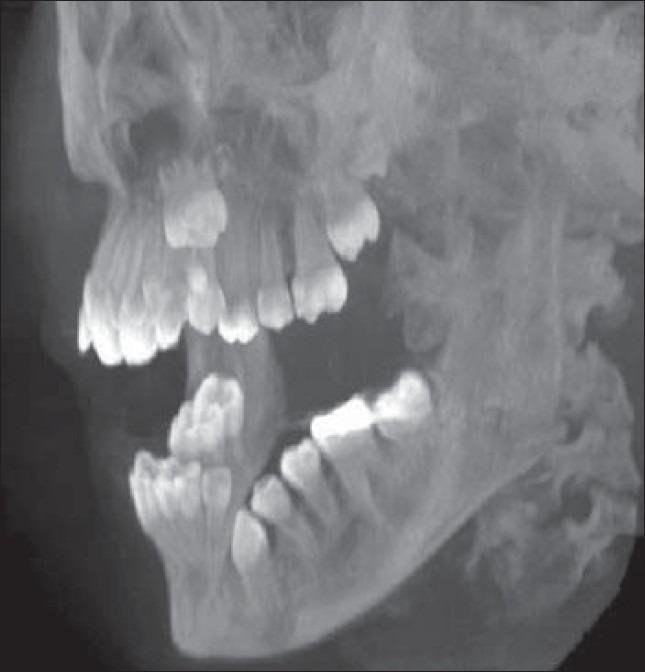

Dentigerous cyst may be developmental or inflammatory in origin. The latter is found only in mixed dentition with a low frequency. Treatment of inflammatory type of dentigerous cyst in children should be done with the aim of saving developing permanent teeth which should not be sacrificed as far as possible. This is a case report of a large inflammatory dentigerous cyst in a 10-year-old female patient treated conservatively by marsupialization method saving all teeth (mandibular permanent left canine, first and second premolars) in relation to the cyst.

Inflammatory dentigerous cyst in a ten-year-old child.